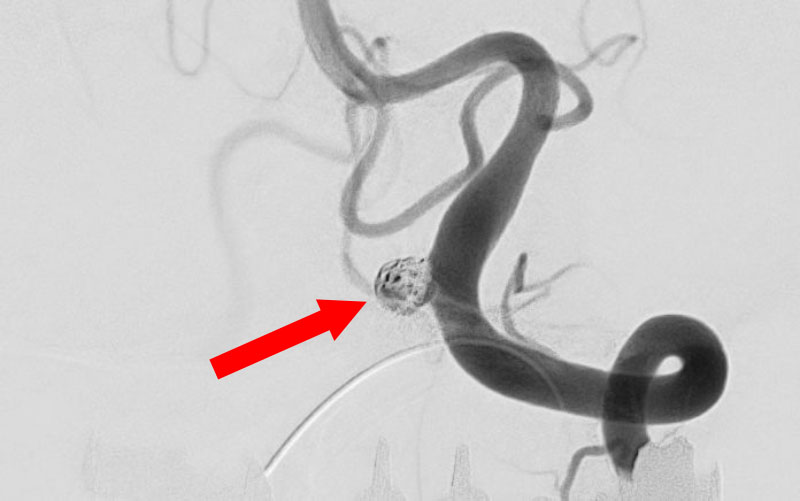

No.1631 手術前